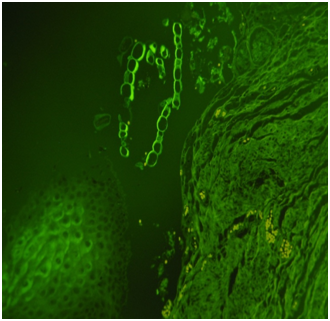

The determination of chemical substances present in the drowning medium could be a complementary tool in the forensic investigation.1,2 Referring to this, both strontium (Sr) and silicon (Si) have proven to be interesting in the diagnosis of drowning (D), in addition to the histological and SEM plankton research in lower airways (Figure 1,Figure 2)(Table 1).

Figures 1 Plankton bolus in the alveolar duct (drowning in freshwater), ordinary (Figure A) and polarized light (Figure B) (EE, 480X).

Histology: Acute emphysema was the prominent observation; edema and hemorrhages were also present.4 In 9 cases (Figures 3-6), exogenous material in the airways, comprehensive of planktonic boli in the lower branches, clearly demonstrable at polarization microscope (and possibly confirmable at SEM’s elemental analysis with EXD). Zoo- and phytoplankton have been better identified in the UV microscope. It is mandatory to differentiate the planktonic material from gastric content, regurgitated and aspirated (Figure 7 & 8).